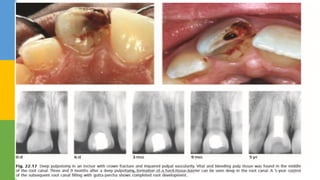

 LUNDY AND STANLEY (1969):Speed of bacterial

INVOLVING DENTIN